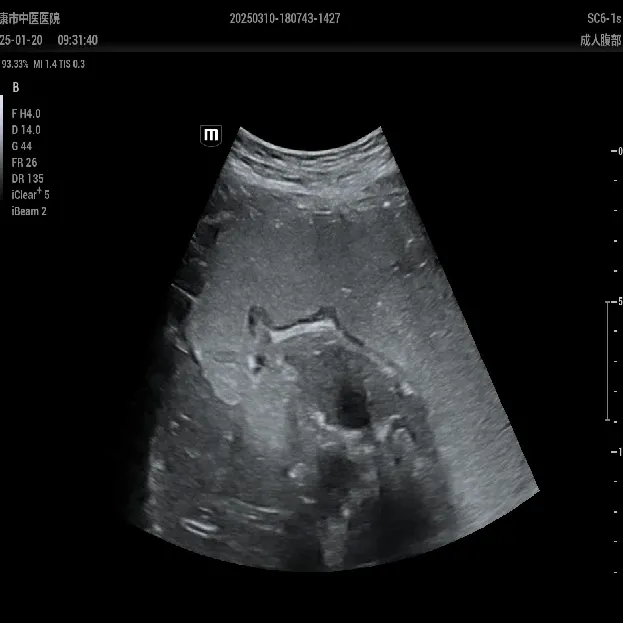

术前CT提示:双侧髋关节脱位,股骨近端畸形,股骨颈、股骨头短小,真臼未发育

术后复查骨盆正位片:髋关节假体位置良好,粗隆下截骨处愈合良好